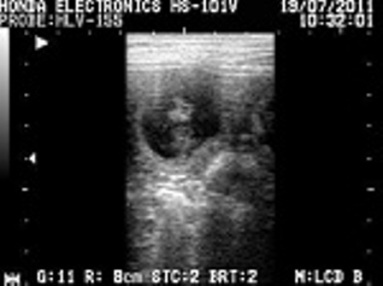

Tragbares Ultraschallgerät zur Trächtigkeitsdiagnose und -

überwachung von Stuten, Hündinnen und Katzen.

Besamung und Besamungskontrolle von Stuten und Hündinnen.